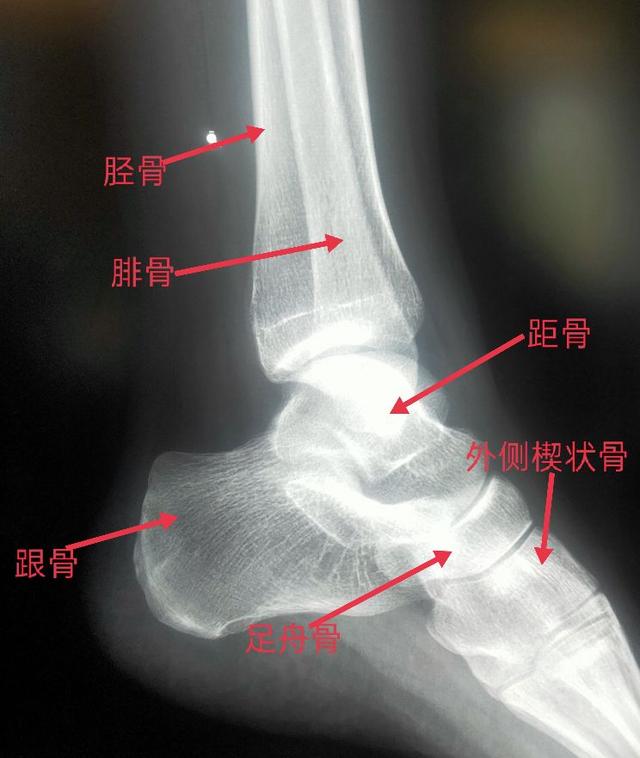

踝关节侧位片可以看到胫骨远端、腓骨远端、后踝、跟骨、距骨、足舟骨、外侧楔状骨。

脚踝是哪个部位图解,脚踝是哪个部位图解视频(学习《X线读片指南》骨、关节系统——踝关节)